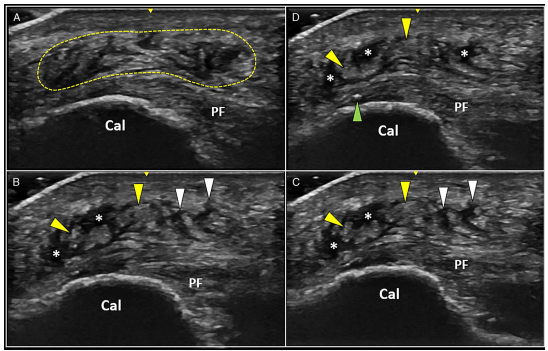

이때는 초음파상에서

지방층의 부종이 관찰되고

육안상으로 피부가 붉어지기도 해요.

이 두 단계를 구분하기 위해,

단순히 손으로 누르는 대신

실시간으로 초음파를 보며 누르는

'소노-팔페이션 (Sono-palpation, 초음파 촉진)'

진단이 필요합니다.